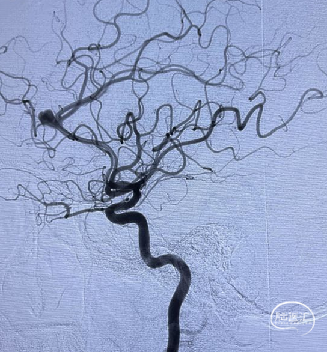

后循环造影